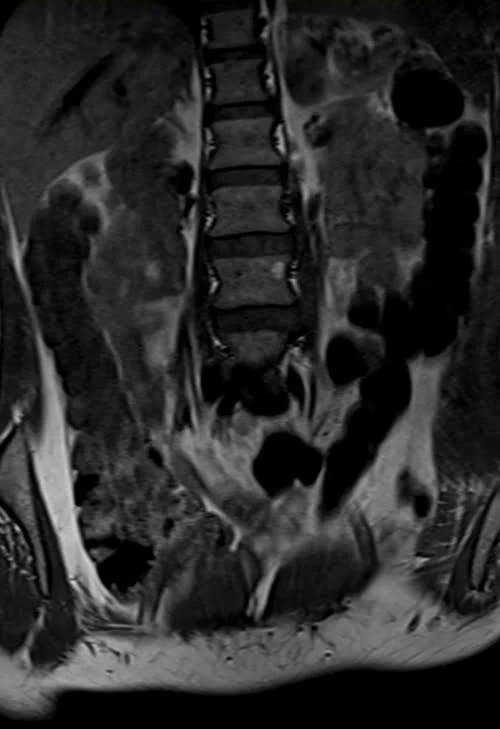

L plexus mri T1 coronal images